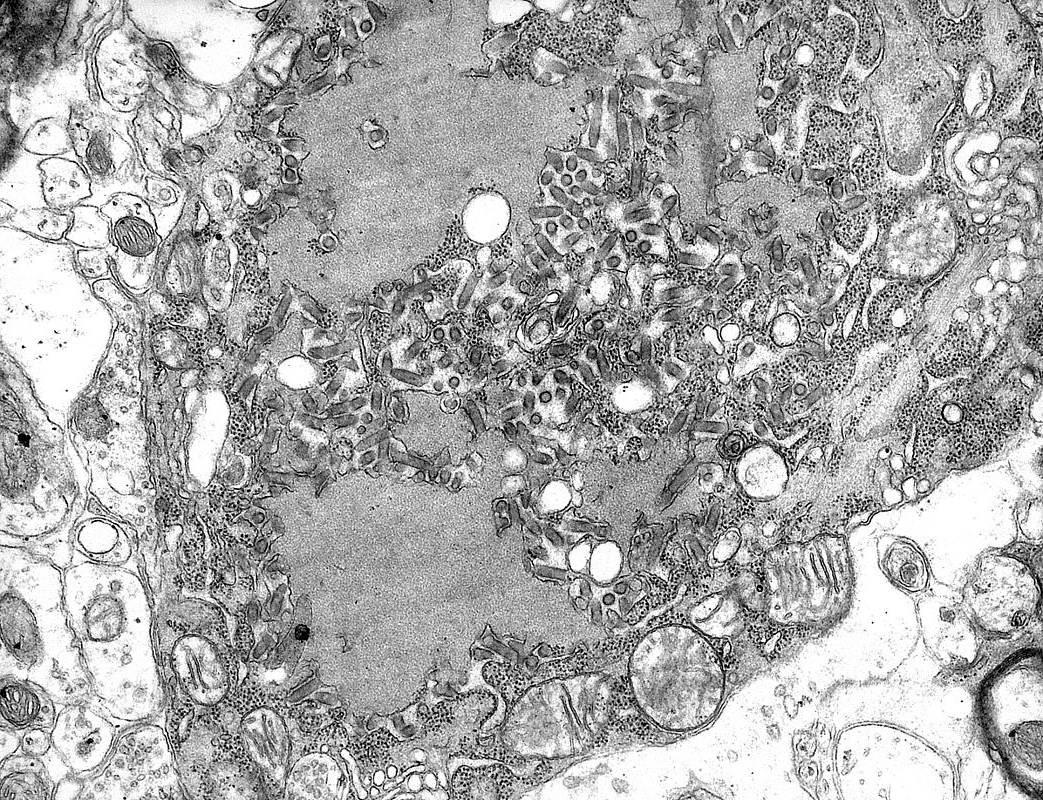

| Электронная микрофотография вируса бешенства и новообразования в цитоплазме нейронов головного мозга, вызванные размножением вируса. |